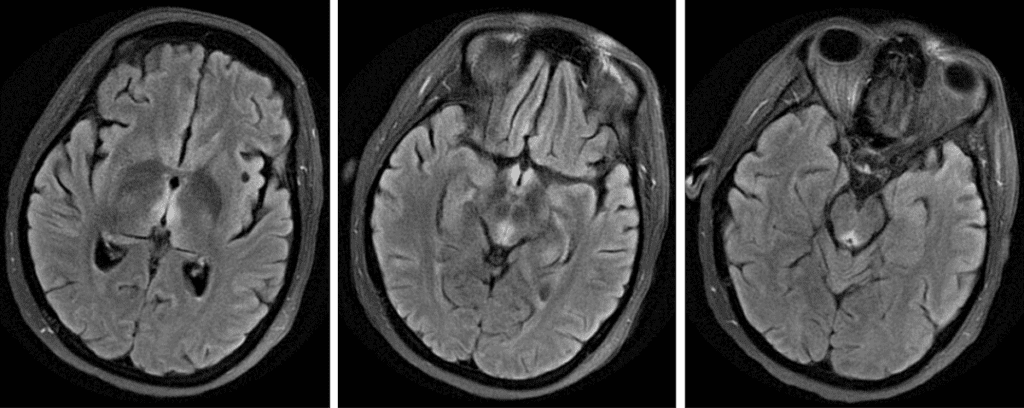

Wernicke Encephalopathy

Look for symmetric T2 hyperintensity in the medial thalami, hypothalami, mammilary bodies, and periaqueductal grey matter.

The classic triad of ataxia, oculomotor abnormalities and confusion is present in the majority of patients.

Over 20% of thiamine deficiencies occur in nonalcoholics with malnutrition, malabsorption, prolonged vomiting, cancer, or AIDS.

MRI is normal in 40% of cases.

Classic imaging appearance should trigger thiamine supplementation due to low-risk and high clinical impact.